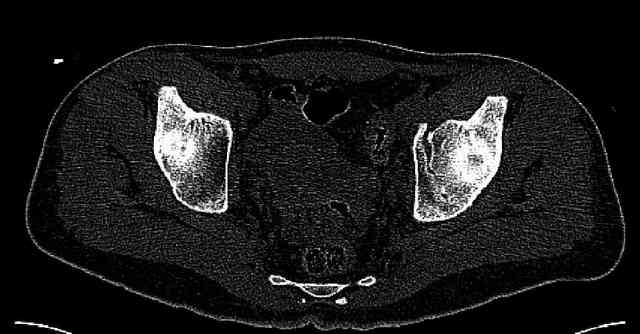

The last two images from the 3-D CT scan certainly makes the fracture look worse than the plan radiographs.

Some more images. Does it help to guess which part of the acetabulum is displaced?

Normal appearing SI joints and a healed posterior column limb... my bet's on caudal segment displacement.